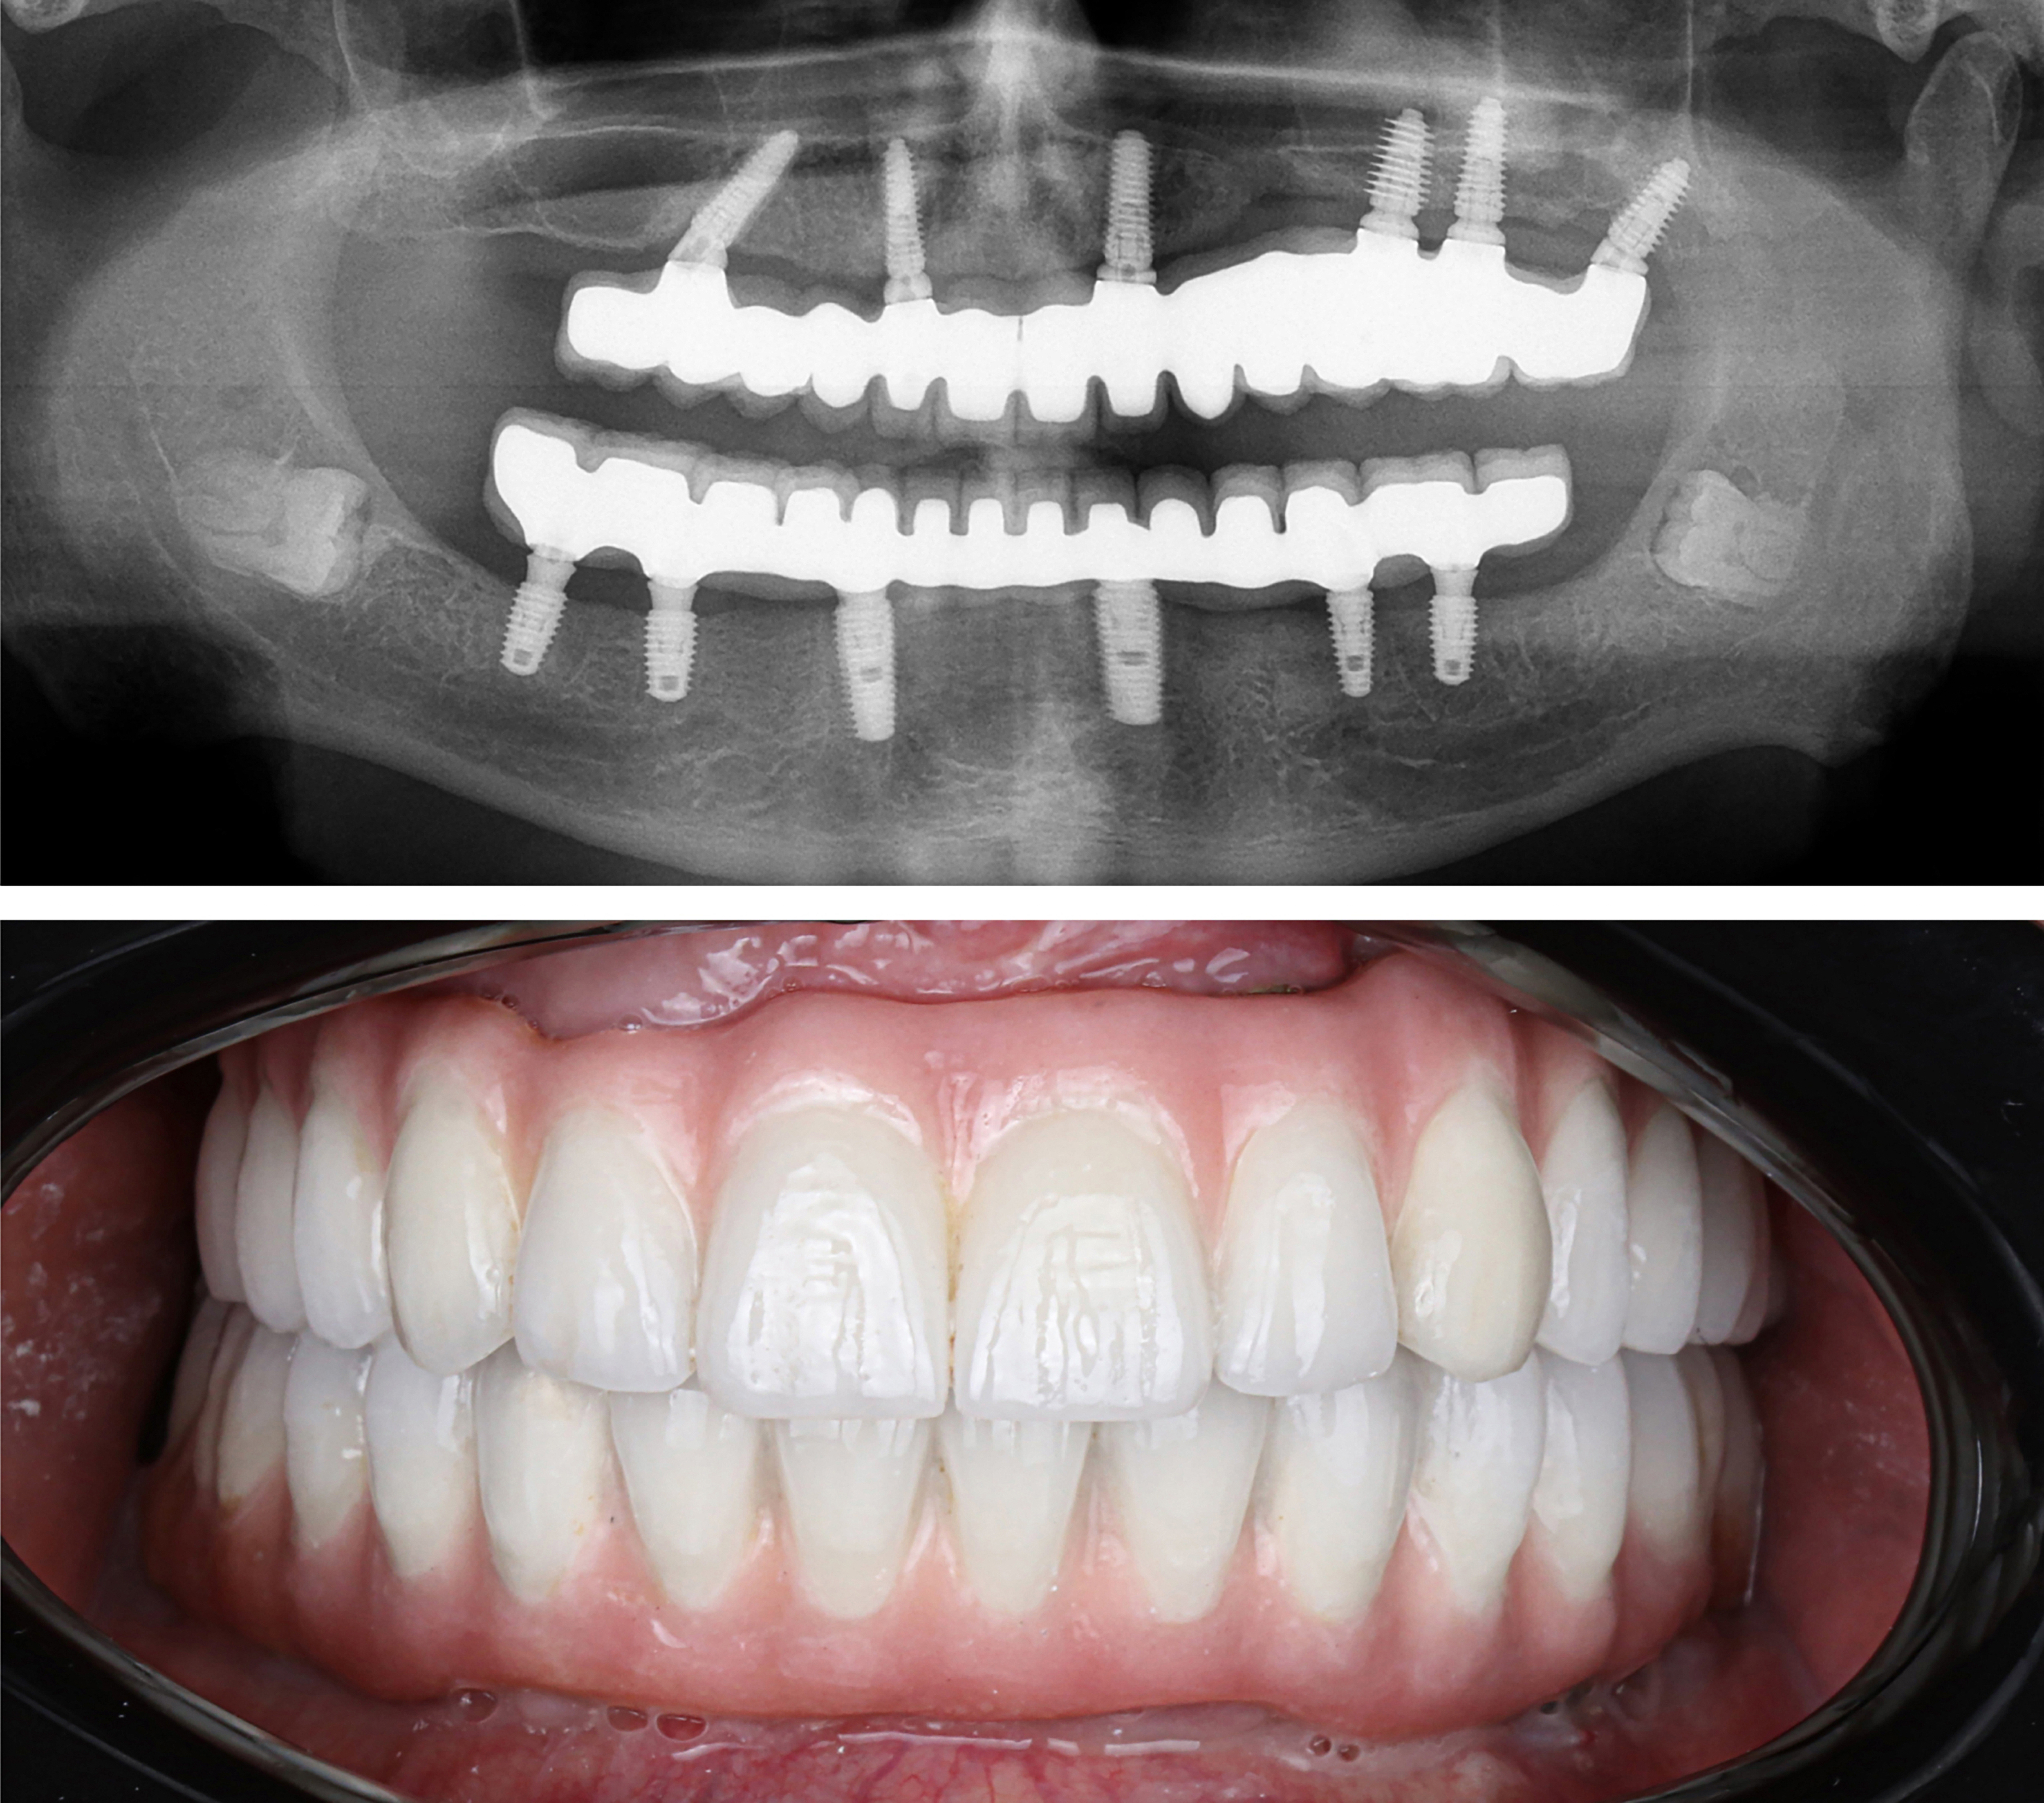

Example transformations achievable with dental implants

Includes surgical placement of 4 to 6 implants.

Includes final ultra aesthetic teeth.

Includes final zirconia teeth.